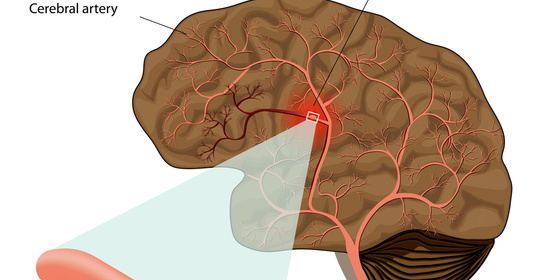

顱腦損傷後頭痛:原因、治療與就醫建議

顱腦損傷後頭痛:原因與處理方法

顱腦損傷後頭痛:原因及處理方式